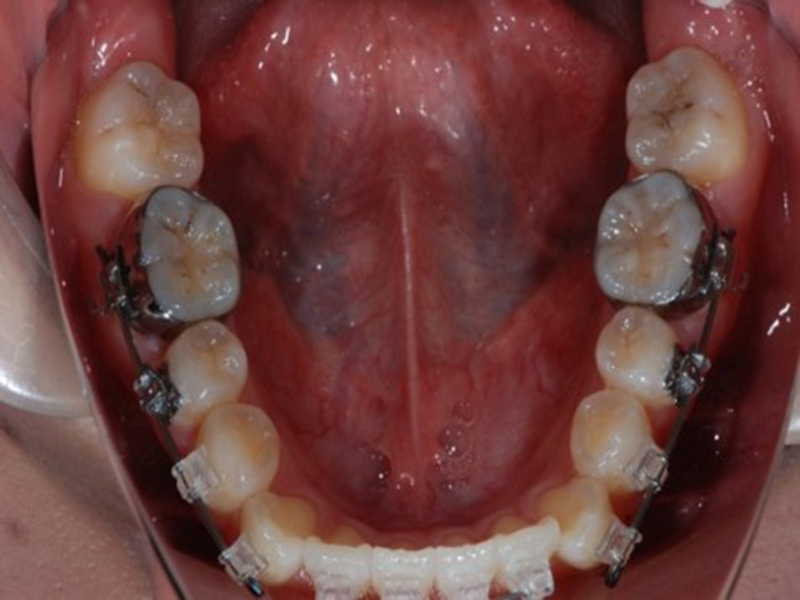

経過